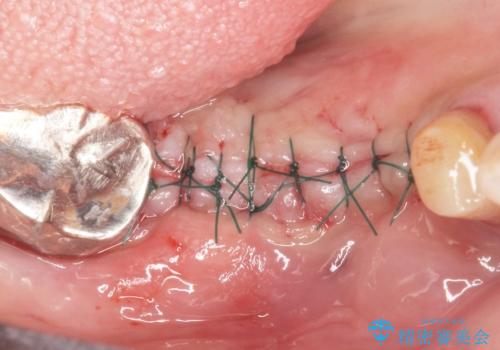

精査したところ、右下4の根尖病変及び右下5の欠損を認め、右下6は残根となり保存不可能な状態でした。

保存不可能な歯を抜去後、インプラント治療と根管治療を行いました。